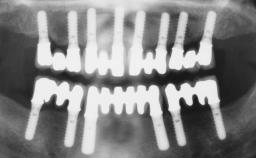

Immediate Loading of Six Implants in the Maxilla and Final Restoration with a Full-Arch CAD/CAM Zirconia FDP

# of Implants 6

Type of Implants One-Piece

Defining Characteristics Fully edentulous upper jaw to be rehabilitated with four or more implants

Modality 6+ implants with immediate loading

Loading Protocol Immediate